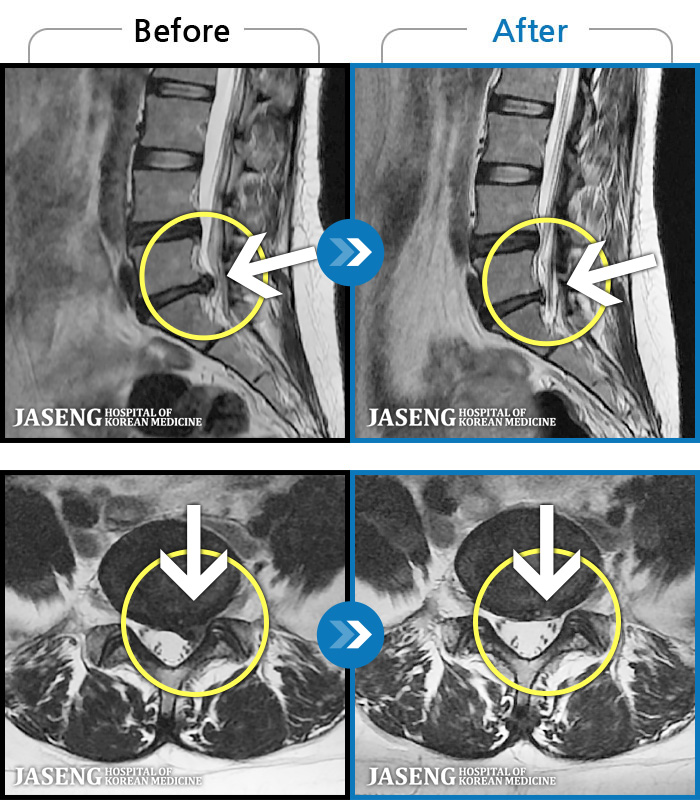

Before

After

통증으로 아기를 안지 못하던 여자분입니다

2023.11.08 ~ 2024.07.29